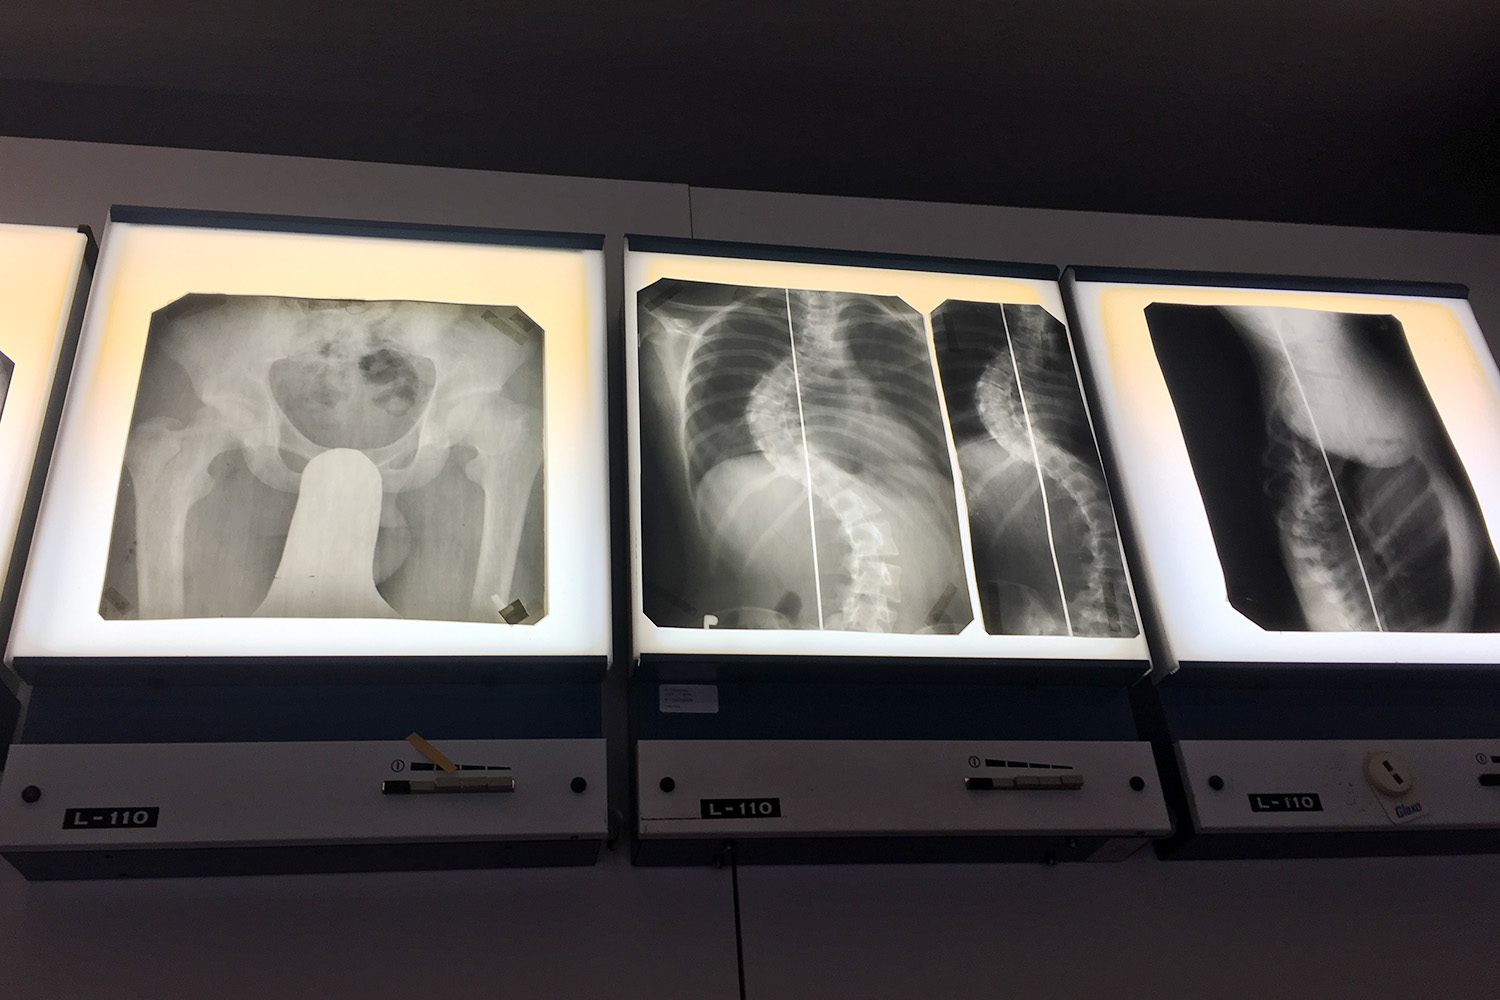

Visí zde například rentgenové snímky. „Těch snímků jsme tady měli na tuny. Za celou dobu existence léčebny se archiv v minulosti nelikvidoval. Tady byly snímky za sto let,“ říká ředitel Hamzovy odborné léčebny Václav Volejník.